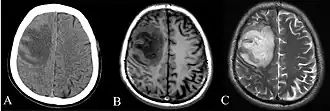

CT and MRI scans showing lesion of the left frontal lobe of the brain.[6]

Depending on the course of infection, other severe manifestations develop. Approximately 1 to 5% of those infected develop inflammation of the brain and brain covering or brain abscess; 14 to 28% develop pyelonephritis, kidney abscess or prostatic abscesses; 0 to 30% develop neck or salivary gland abscesses; 10 to 33% develop liver, spleen, or paraintestinal abscesses; and 4 to 14% develop septic arthritis and osteomyelitis.[1] Rare manifestations include lymph node disease resembling tuberculosis,[10] mediastinal masses, pericardial effusion,[3] mycotic aneurysm,[1] and inflammation of the pancreas.[3] In Australia, up to 20% of infected males develop prostatic abscess which may manifest clinically as pain during urination, difficulty in passing urine, and urinary retention requiring catheterisation.[1] Rectal examination may find enlarged prostate.[3] In Thailand, 30% of the infected children develop parotid abscesses.[1] Encephalomyelitis not only happens in those with risk factors but can also occur in healthy people without risk factors. Those with melioidosis encephalomyelitis tend to have normal computed tomography (CT) scans but increased T2 signal by magnetic resonance imaging (MRI), extending to the brain stem and spinal cord. Clinical signs include: unilateral upper motor neuron limb weakness, cerebellar signs, and cranial nerve palsies (VI, VII nerve palsies and bulbar palsy). Some cases presented with flaccid paralysis alone.[3] In northern Australia, all melioidosis with encephalomyelitis cases had elevated white cells in the cerebrospinal fluid (CSF), mostly mononuclear cells with elevated CSF protein.[10]

Various imaging modalities can also help with the diagnosis of melioidosis. In acute melioidosis with the spreading of the bacteria through the bloodstream, the chest X-ray shows multifocal nodular lesions. It may also show merging nodules or cavitations. For those with acute melioidosis without the spread to the bloodstream, chest X-ray most commonly shows upper lobe consolidation or cavitations.[10] In chronic melioidosis, the slow progression of upper lobe consolidation of the lungs resembles tuberculosis.[10] For abscesses located in other parts of the body apart from the lungs, especially in the liver and spleen, CT scan has higher sensitivity when compared with an ultrasound scan. In liver and splenic abscesses, an ultrasound scan shows "target-like" lesions while a CT scan shows "honeycomb sign" (abscess with loculations separated by thin septa) in liver abscesses.[10] For melioidosis involving the brain, MRI has higher sensitivity than a CT scan in diagnosing the lesion. MRI shows ring-enhancing lesions for brain melioidosis.[10]